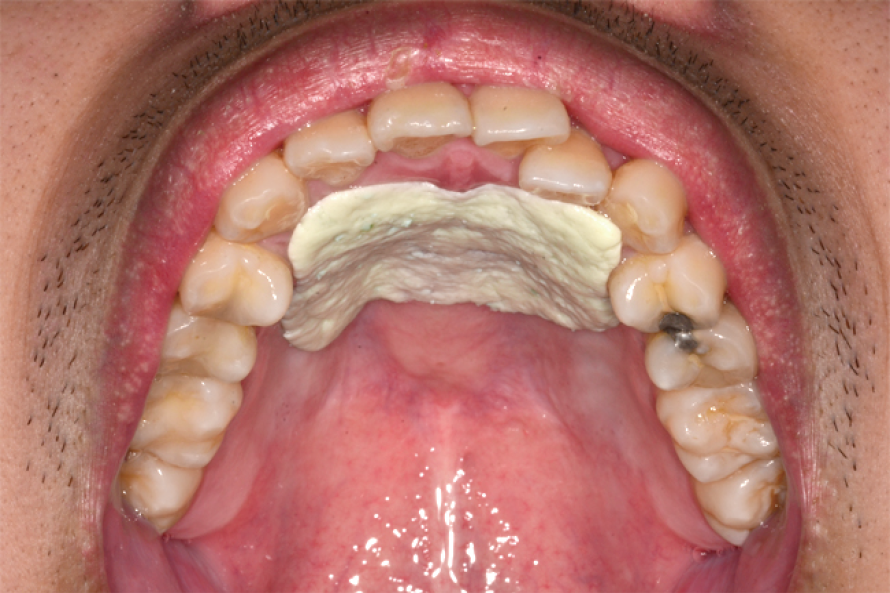

• 用後牙咀嚼口香糖(建議無糖口香糖),在用舌頭將咀嚼過的口香糖滾動至舌尖處(圖一)。

• 利用舌頭往上舉的力量把口香糖推到上顎穹窿的位置(圖二),訓練咬合與吞嚥的動作,保持用舌頭讓口香糖壓在上顎穹窿處(圖三),讓口香糖完全的經過舌頭的壓力平鋪到上顎穹窿處(圖四)。